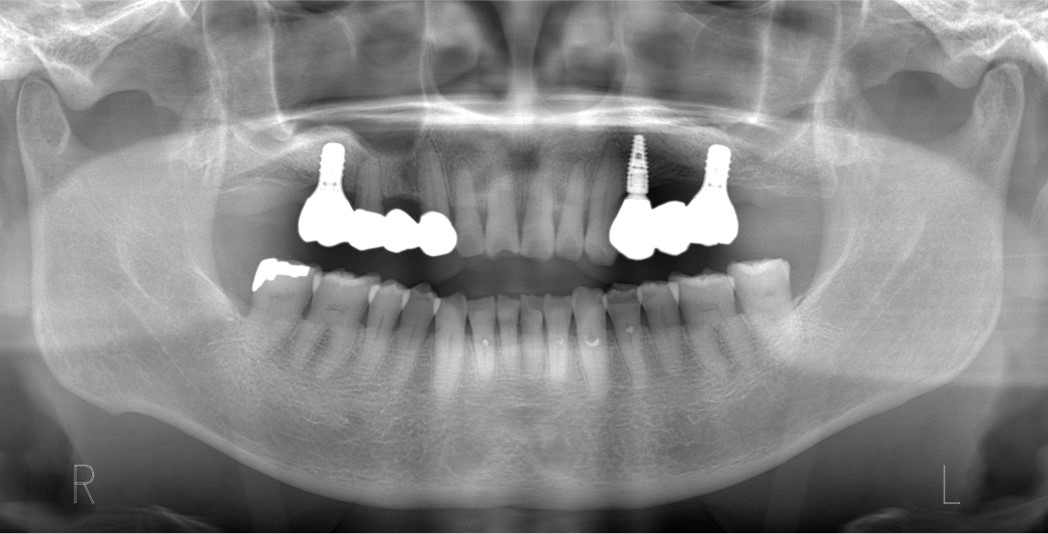

院長は、外科処置に関する口腔外科の専門医資格である公益社団法人日本口腔外科学会認定口腔外科専門医(第2055号)、NPO法人日本口腔科学会認定医(3-16046)、インプラントの専門医資格である公益社団法人日本口腔インプラント学会専門医(第1103号)を持っています。また、インプラントの国際的非営利学術組織 International Team for Implantology (ITI)の日本支部公認インプラントスペシャリスト に認定されています。さらに、全国規模のインプラント治療シンポジウム(医療関係者向け)、地域でのインプラント治療セミナーなどで講師を務めており、歯科医師や歯科衛生士に対する教育活動を行っています。

インプラント治療は外科処置を伴うためにリスクがあります。下顎の神経(下歯槽神経)を傷つけないように、上顎の骨の空洞(上顎洞)に突き抜けないように計画します。ゆえに、歯科医師は、最新の知識による十分な検査と確かな診断ができ、技術に熟練している必要があります。

インプラントと関連処置の内容と費用をまとめます。当院では、症状(骨の状態、インプラント本数など)と患者さんの希望を十分に考慮したうえで、医学的根拠にもどつく最適な治療をお勧めします。